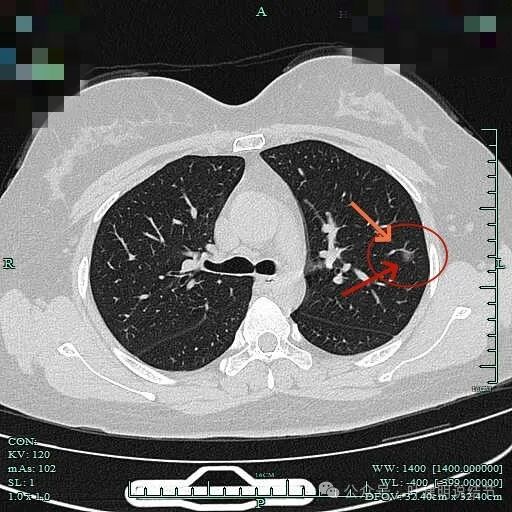

边缘区域病灶有微小血管进入,也有细支气管扩张征。

左肺这个病灶虽然不大,但这么小的而且没有纵隔窗可见的实性成分情况下,却有以下倾向风险高的影像特征:1、细毛刺征;2、血管穿行;3、血管弯征;4、邻近血管改变走行方向进入病灶;5、灶内细支气管扩张。这些都说明病灶一是对血供有要求,二是有与密度明显不符的收缩力和对周围结构的影响力!所以我认为此灶一是必为恶性,二是至少是微浸润性腺癌,也可能会是浸润性腺癌。再加上随访持续存在以及位置靠肺外周能楔形切除,所以建议她切了放心。